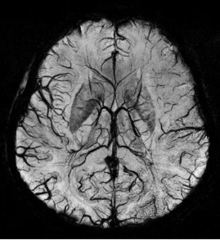

An SWI venogram of a neonate with Sturge-Weber syndrome who did not display neurological symptoms is shown to the left. The initial conventional MR imaging methods did not demonstrate any abnormality. The abnormal venous vasculature in the left occipital lobe extending between the posterior horn of the ventricle and the cortical surface is clearly visible in the venogram. Due to the high resolution even collaterals can be resolved.